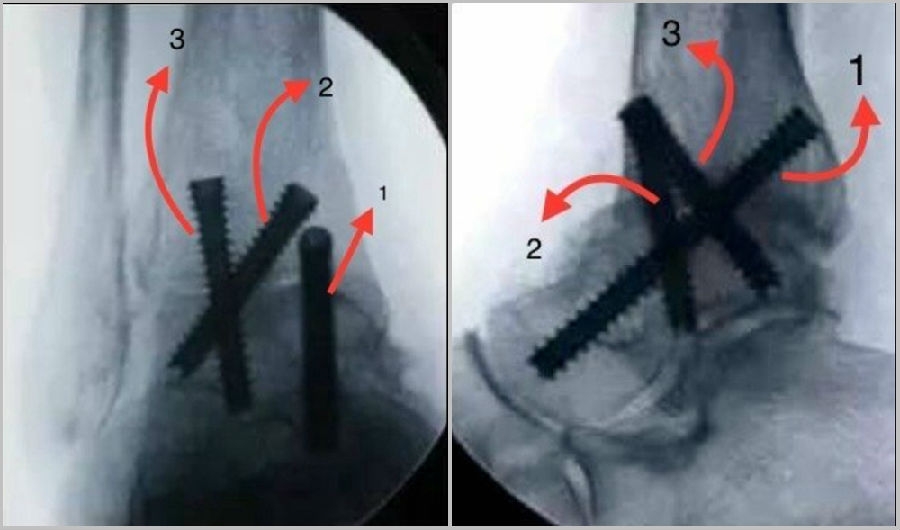

③固定

1枚螺钉自内踝后侧向前下方向打入距骨头颈部;

2枚螺钉自前内踝斜向下至距骨体部;

3枚螺钉自胫骨远端前外侧向距骨体后内侧。